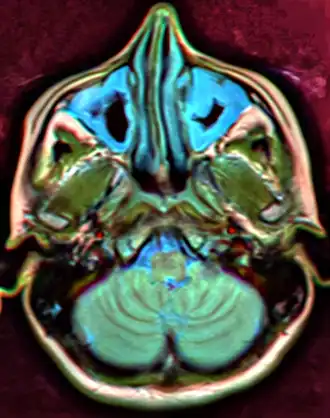

For sinusitis lasting more than 12 weeks, a CT scan is recommended.[66] On a CT scan, acute sinus secretions have a radiodensity of 10 to 25 Hounsfield units (HU). In a more chronic state, they become more viscous, with a radiodensity of 30 to 60 HU.[69]

-

CT of chronic sinusitis -

MRI image showing sinusitis. Edema and mucosal thickening appear in both maxillary sinuses. -